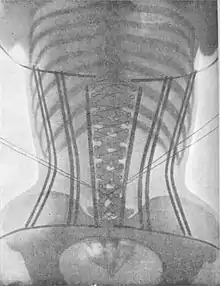

Health effects

The negative physical effects of corseting have become widely known, including a variety of myths. For example, the idea that Victorian women frequently underwent rib removal to achieve a smaller waist is baseless.[10] However, wearing a corset does affect a number of bodily functions and can be deleterious to the wearer's health, especially when worn regularly over a long period of time; during the Victorian era stays were typically begun at or before the onset of puberty, with reported ages ranging from 7 to 13.[5]

Muscular wasting

Corsets are known to contribute significantly to muscle wasting in the core and back when worn over long periods of time. Although they temporarily relieve back pain, muscle atrophy due to disuse will lead to increased lower-back pain and eventually reliance on the corset.[10] Forceps delivery was standard during this period, which could be due to atrophy of the abdominal muscles caused by lifelong corset usage.[12]

Pelvic floor and reproductive health

A significant source of the controversy surrounding corsets was their ability to affect the reproductive organs due to the downward pressure created by displacement of organs.[5] Corsets were usually worn during pregnancy, often as long as possible.[10]: 76 Obstetrician and writer Alice Bunker Stockham campaigned against the widespread practice of wearing corsets during pregnancy, writing sardonically: "The corset should not be worn for two hundred years before pregnancy." Reformist and activist Catharine Beecher was one of the few to defy propriety norms and discuss in any detail the gynecological issues resulting from lifelong corset usage, in particular uterine prolapse.[16][17] Feminist historian Leigh Summers theorized that some of the moral panic came from the common but unspeakable idea that tightlacing could be used to induce an abortion.[5]

Doctors often attributed the difficult births many Victorian women experienced to corsets, widely believing that "primitive" women who wore less restrictive garments had less painful births and were overall healthier and more vigorous.[5] Modern skeletal analyses indicate that corseting, particularly during pre-puberty (most girls began corseting around 7 or 8), led to underdevelopment of the pelvic inlet, which is consistent with reported difficulties in birth, although studies into this topic have been mixed.[18][13]

Prolapse

Uterine prolapse was a significant danger exacerbated by corsets, the incidence of which correlated with widespread corset wearing.[10][12] Both rectal and uterine prolapse occurred at a higher incidence during the Victorian era than today, with occurrences declining as the corset fell out of fashion.[12] An 1888 doctor reported that “uterine derangement had increased fifty percent within the last fifteen years as a result of tight clothing, corsets and high heels."[5]: 113 This era saw the development of a number of pessaries and other devices patented to support the prolapsed uterus, the insertion of which frequently led to further complications; the topic was a subject of wide professional discussion.[5][13]

Miscellaneous

Corset wearing is known to decrease the size of the stomach and disturb digestion, potentially leading to constipation or indigestion. The downward pressure on the pelvic floor can also lead to urinary incontinence, similar to that experienced during pregnancy.[10]